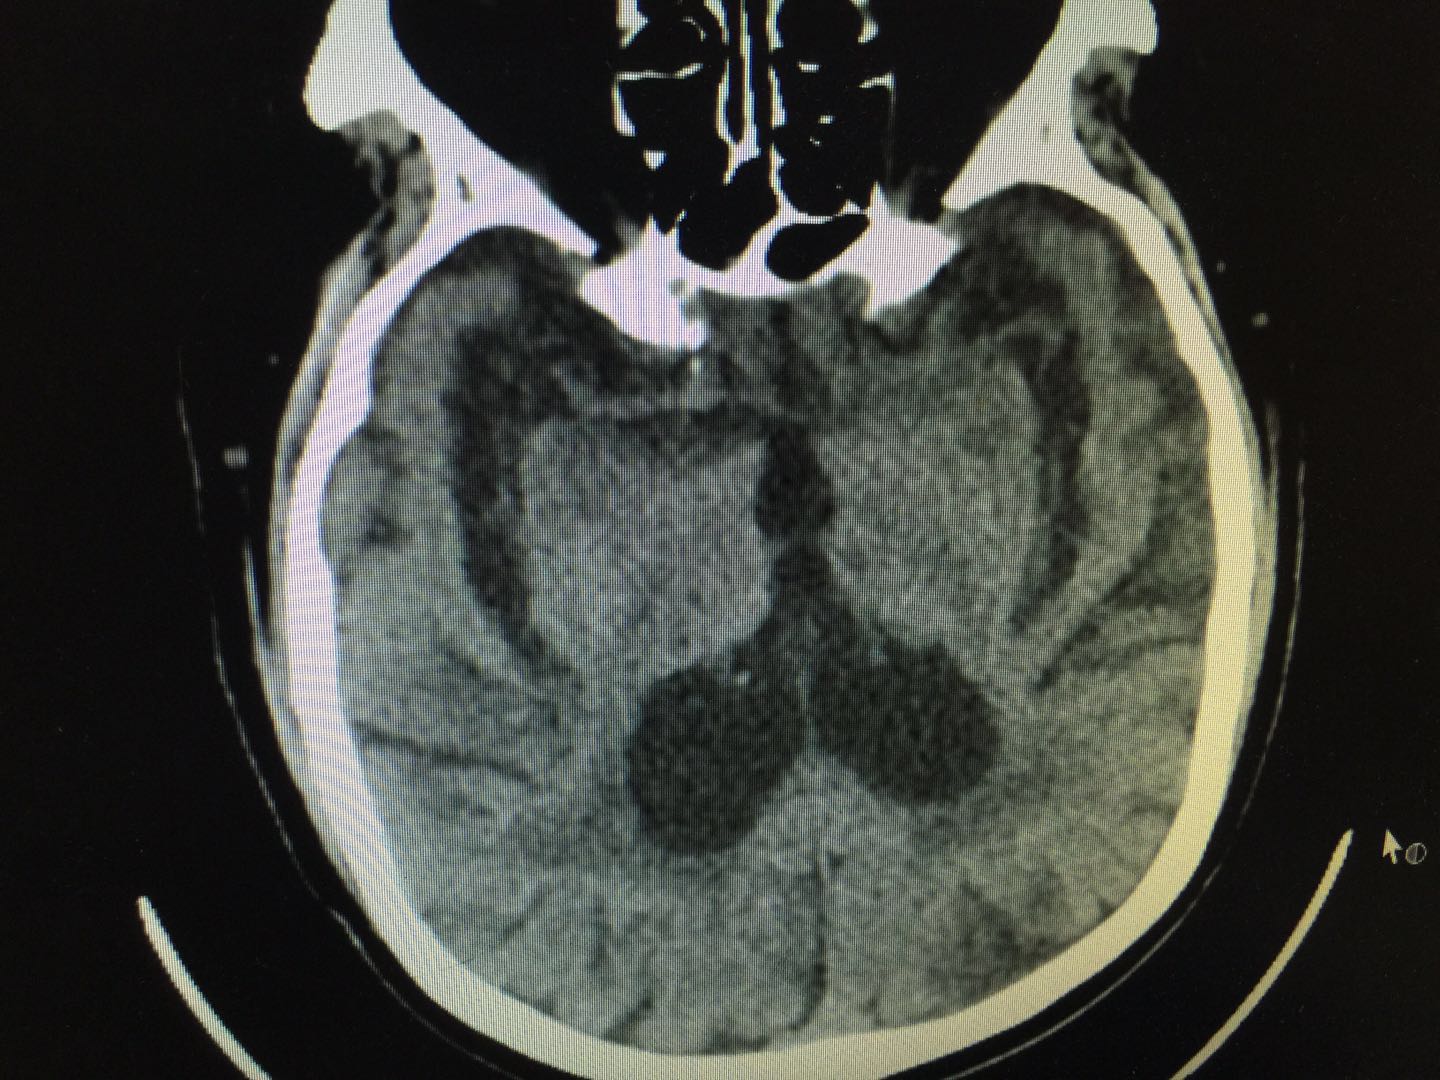

脑萎缩,是一种年龄相关的退行性病变,是老年人最常见的慢性病之一,其中最常见的类型是大家都比较熟悉的阿尔茨海默病,该病表现为以进行性认知功能障碍和行为损害为特征的中枢神经系统退行性病变。临床上主要表现为记忆障碍、失语、失用、失认、视空间能力损害、抽象思维和计算力损害、人格和行为改变等。当患者出现阿尔茨海默病,患者可能会因此失去日常生活能力,需要他人照料和看护,且该病是老年死亡病因的原因之一。一旦患了该病,不仅给患者本身带来巨大痛苦,而且给家庭和社会也带来沉重的负担。

脑萎缩

脑梗死,又称缺血性脑卒中,是由于各种脑血管病变所致的脑部供血障碍,导致局部脑组织缺血、缺氧性坏死,而迅速出现相应神经功能缺损的一类临床综合征。期最常见的原因是动脉粥样硬化,也是和年龄密切相关的一种病理改变。脑梗死如果栓塞到重要部位,也会导致患者突然出现偏瘫、失语等,严重者或者抢救不及时,也会出现死亡。关键部位的脑梗死,同样会导致患者失去日常生活能力,也给患者本人以及家庭带来巨大的经济和精神压力。

脑梗死